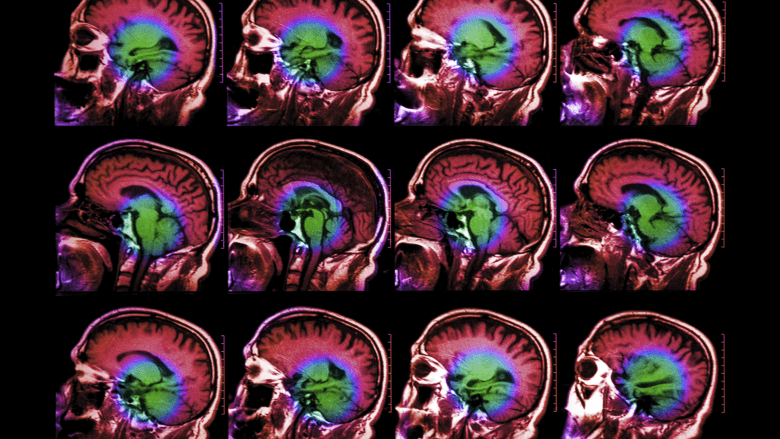

Medical Imaging. Concussions can impair brain functioning but they typically do not cause structural changes to the brain that can be seen with medical imaging. A CT scan or MRI may be ordered as precaution to rule out a blood clot or other injury.